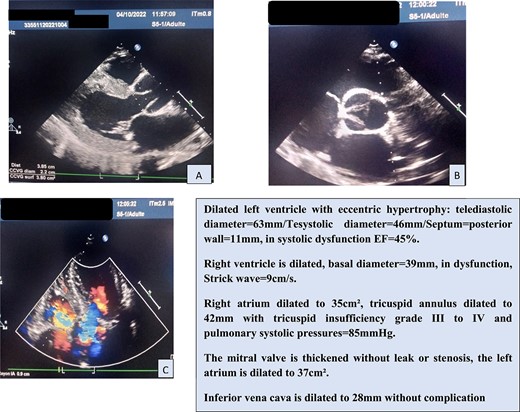

In view of this clinical picture, transthoracic echocardiography (TTE) was performed, which confirmed the significant AI and ascending aorta dilatation (Fig. 1).